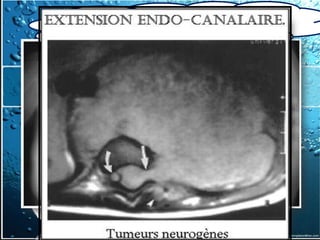

c) IRM thoracique

2-2-Examen Paraclinique – Noninvasifs

2.2.1.1. Imagerie thoracique

IRM n’est utilisé que pour mieux évaluer

l’extension de l’invasion vasculaire ou

cardiaque

Le seul avantage de l'IRM , confirmer la

nature liquidienne d'une lésion dont la

plage est de densité élevée en TDM, ex:

kystes bronchogéniques

IRM > TDM pour l'étude des masses du

médiastin postérieur, pour préciser une

éventuelle extension intracanalaire d'une

tumeur neurogène ou d'un abcès